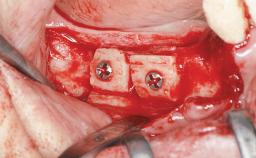

Le Fort I Interpositional Graft and Mandibular Sandwich Osteotomy for Maxillofacial Rehabilitation after Severe Periodontitis

A 47-year-old woman who had suffered from aggressive periodontitis requiring a number of periodontal interventions over more than 10 years was referred by her general dental practitioner and periodontologist for bone augmentation and implant therapy. Her failing dentition had already been scheduled for extraction. The patient expressed a desire for implant-supported fixed restorations and esthetic improvement of her lower face. She had agreed to consult with a maxillofacial surgeon after the referring dentist had suggested bone augmentation. An initial examination by the maxillofacial surgeon revealed mobility of all residual teeth in a patient who was very unhappy with the function of her removable partial dentures. Due to periodontally migrated flaring teeth and loss of occlusal support, the vertical dimension of occlusion was dramatically reduced. The patient was displeased with her lower face because of deepened nasolabial, commissural, and supramental folds.

Bone Augmentation Horizontal|Sinus Floor Elevation|Staged|Vertical

Augmentation Materials Autogenous chips|Autogenous block(s)|Xenogenous|Membrane

Bone Volume Deficient vertically or deficient vertically AND horizontally